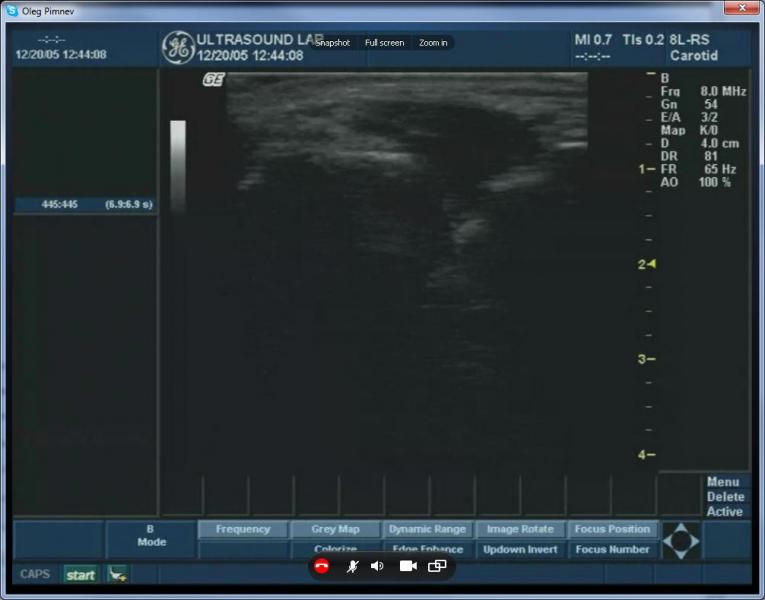

下圖顯示了超聲波機器的VGA輸出可以被注入和流傳輸到Skype視頻電話會議

以下截圖是來自Skype超聲波圖像的廣播視頻:

在這個屏幕截圖、視頻從一個GE Logiq

Book在網絡實時廣播到遠程參與者。

在上面的截圖中,

由于Skype視頻壓縮可以看到典型的色塊發生。不幸的是,因為Skype沒有視頻質量控制的選擇,沒有辦法擺脫他們。